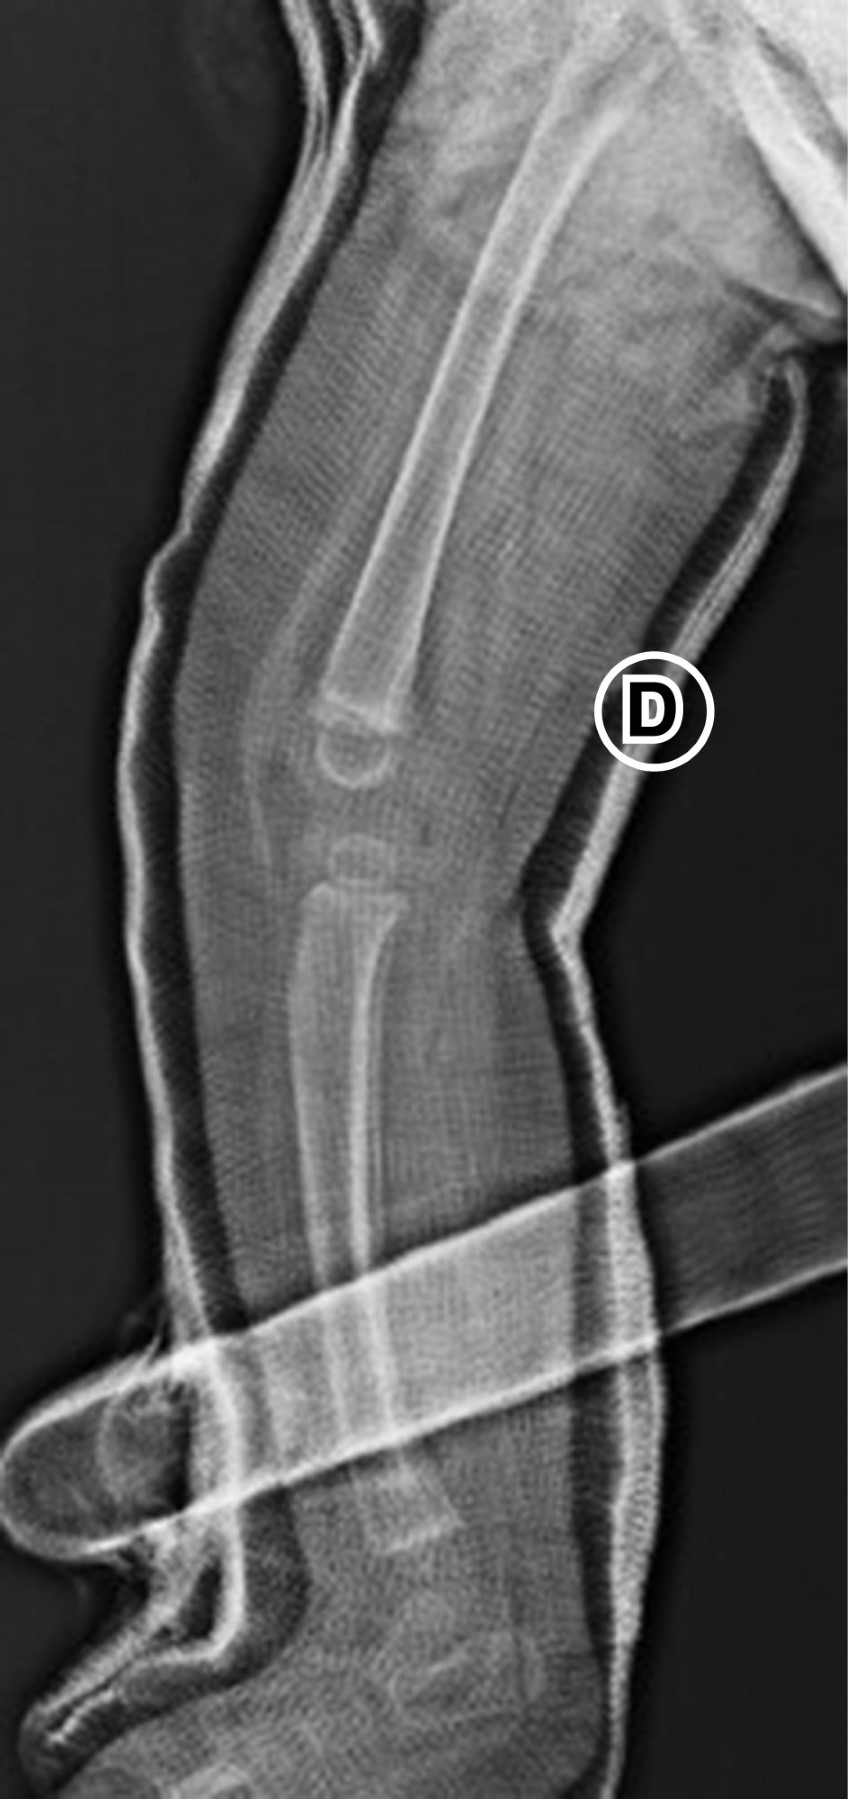

Multiple fractures caused by dystonia and muscular spasms in a patient with mitochondriopathy homozygous ECHS-1 gene mutation

Mitochondriopathies are rare genetic mutations of mitochondrial nuclear DNA that affect primarily the respiratory chain, decreasing the production of cellular ATP. These mutations can be de novo or congenital and have a broad spectrum of clinical presentations. They were first reported in 1958 and four to five new cases are reported per 100,000 births annually. They manifest more frequently as symptoms in organs with high energetic demand and are a diagnostic challenge due to the heterogeneity of clinical manifestations. We present the case of a 16-month-old patient with homozygous deletion mutation of ECHS-1 and glucose-6-phosphate dehydrogenase deficiency. ECHS-1 deficiency has been reported in less than 30 cases worldwide. The deletion manifests in the present case as psychomotor retardation, gastroesophageal reflux, dystonia of difficult control and muscle spasms that have twice caused traction fractures in metaphysis of long leg bones.

Figure 1